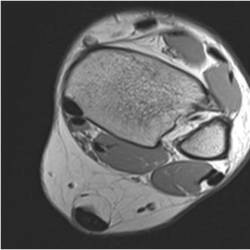

Gallery of Unlabled Radiographs from Lecture (Dr. French) - 2020

Click a thumbnail to enter the gallery display. Click the file name link at the bottom left of the gallery display to view the image at high resolution.